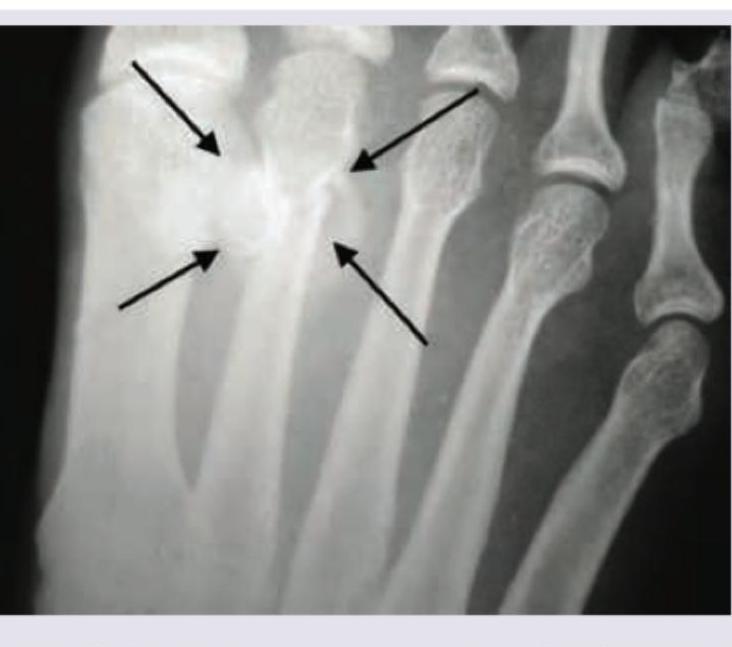

Identify the fracture shown in the image below:

Explanation: ***Jones fracture*** - The image indicates a fracture located at the **proximal metaphyseal-diaphyseal junction of the fifth metatarsal**, which is characteristic of a **Jones fracture**. - This fracture involves the **base of the fifth metatarsal** and is often associated with a higher risk of nonunion due to limited blood supply. *March fracture* - A **March fracture** is a type of stress fracture, typically affecting the **shaft of the second, third, or fourth metatarsals**, often seen in military recruits or those who engage in prolonged walking or running. - It results from repetitive stress rather than an acute injury, and its location is distinct from the proximal fifth metatarsal. *Shepherd's fracture* - A **Shepherd's fracture** refers to an avulsion fracture of the **posterolateral tubercle of the talus**, also known as an os trigonum fracture. - This fracture is located in the ankle region, distinct from the metatarsals. *Cotton's fracture* - A **Cotton's fracture** is a trimalleolar fracture of the ankle, involving the **medial malleolus**, **lateral malleolus**, and the **posterior malleolus** of the tibia. - This is a complex ankle injury, entirely unrelated to fractures of the metatarsals.

Explanation: ***March fracture*** - The image indicates a **stress fracture** of a metatarsal bone, which is characteristic of a **March fracture**. - This type of fracture commonly affects the **2nd or 3rd metatarsal** and is often seen in individuals who engage in strenuous physical activity. *June's fracture* - This is not a recognized eponym for a specific type of fracture in the foot. - The term "June's fracture" does not correspond to any known medical diagnosis related to metatarsal stress fractures. *Shepherd's fracture* - A Shepherd's fracture refers to a **fracture of the posterior process of the talus**. - It is distinct from a metatarsal stress fracture and typically results from forced plantarflexion. *Cotton's fracture* - A Cotton's fracture is a **trimalleolar ankle fracture**, involving the medial, lateral, and posterior malleoli of the ankle. - This is a complex ankle injury, unrelated to a metatarsal stress fracture.